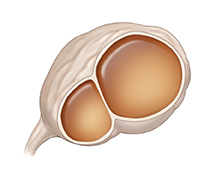

Cistoadenoma benigno

Si la cápsula que rodea el ovario crece, puede formar un cistoadenoma. Estos quistes pueden crecer en uno o en ambos ovarios. Por lo general, no causan síntomas si son pequeños. Pero si crecen, pueden ejercer presión contra los órganos que están cerca de los ovarios y causar dolor. También pueden causar dolor por estirar la cápsula del ovario. Un quiste que empuja la vejiga puede provocar ganas frecuentes de orinar. En ocasiones, estos quistes se rompen y sangran.